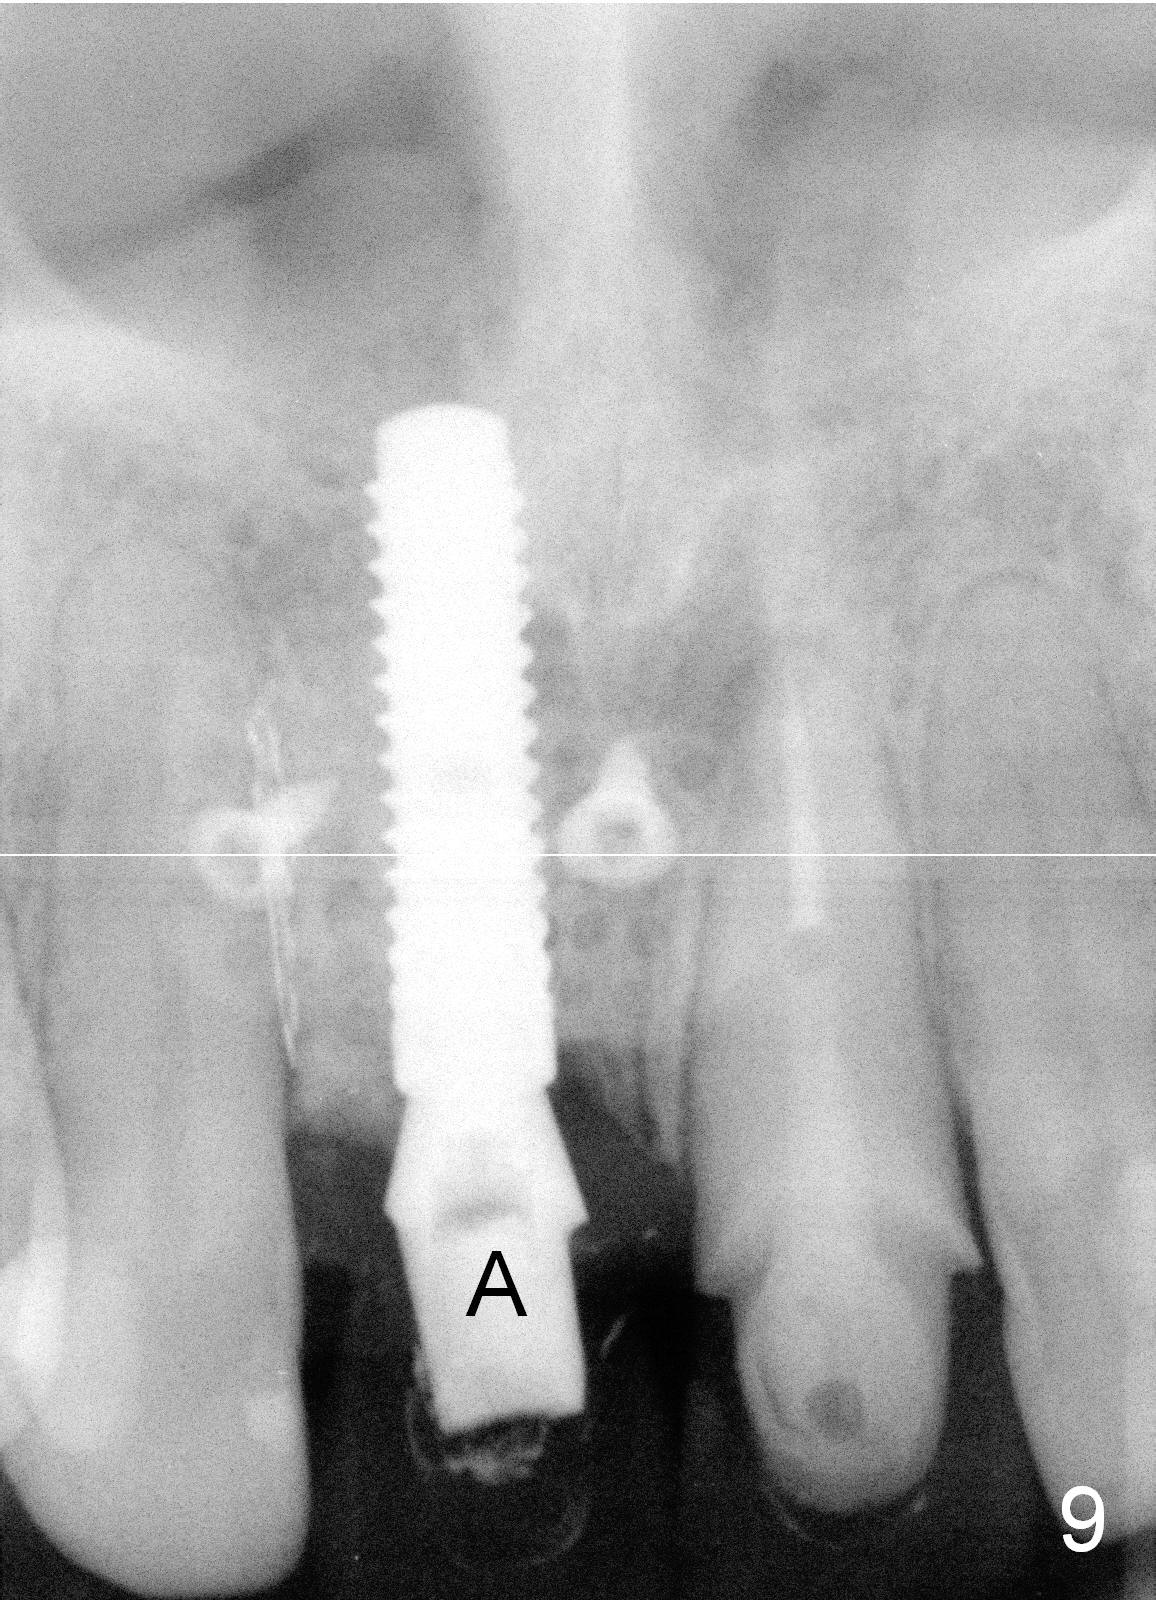

To correct the gingival margin associated with #8 implant, bone graft is needed.  Particulate graft may not stay in place. Chin graft is harvested.  Since the roots of the lower anterior teeth are long (Fig.8), the width of the chin graft is limited for direct screw fixation (Fig.9,10).  Titanium mesh is used for fixation of the graft.  Connective tissue graft from the palate is to increase bulk at the site of #8 (Fig.11 *).  There is no symptom or sign of infection 1 month postop (Fig.12,13).  Although there is alteration of sensation of the lower incisors, there is no apical radiolucency of them 4 months postop (Fig14).  There is no abnormality associated with the bone graft and Titanium mesh (Fig.15).